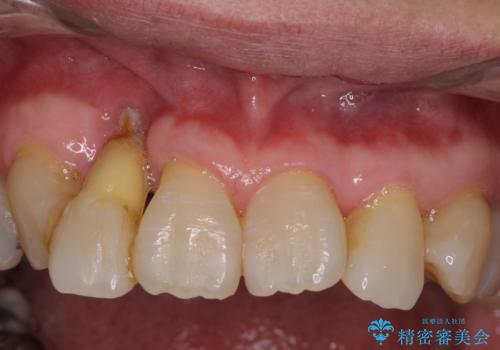

- 歯の欠損や歯肉からの出血などを気にして来院された患者様です。

診査の結果、歯周病であることが分かり、抜歯が必要な歯も見受けられました。

骨造成やインプラント、歯周外科、歯肉移植、矯正など、多くの処置を組み合わせて治療を行うこととしました。